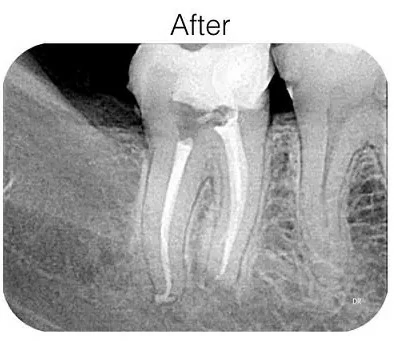

Root Canal Treatment / Rotary Endodontics At Shinas Dental Clinic Barka.

Root Canal Treatment Is A Procedure Used To Treat Infected Or Damaged Tooth Pulp, Which Is The Inner Part Of The Tooth Containing Nerves And Blood Vessels. Shinas Dental Clinic We Offer Advanced Rotary Root Canal Therapy To Effectively And Efficiently Treat Root Canal Infections And Save Damaged Teeth. During The Procedure, The Dentist Uses Rotary Instruments To Clean And Shape The Root Canal System Thoroughly. This Advanced Technology Allows For More Precise Cleaning And Shaping Of The Canals, Leading To Better Outcomes And Reduced Treatment Time. Rotary Root Canal Therapy At Shinas Dental Clinic Offers Several Benefits: Efficient Cleaning: Rotary Instruments Enable Thorough Cleaning Of The Root Canal System, Removing Infected Tissue And Bacteria Effectively. Precise Shaping: The Instruments Allow For Precise Shaping Of The Canals, Ensuring Better Sealing Of The Tooth After Treatment. Reduced Discomfort: The Efficient And Precise Nature Of Rotary Root Canal Therapy Can Lead To Reduced Post-Operative Discomfort For Patients. Preservation Of Natural Teeth: By Effectively Treating Infections And Saving Damaged Teeth, Rotary Root Canal Therapy Helps Preserve Natural Teeth And Avoid The Need For Extraction. With Our Experienced Team And Advanced Technology, We Provide High-Quality Rotary Root Canal Therapy At Shinas Dental Clinic, Ensuring Optimal Outcomes And Improved Oral Health For Our Patients.